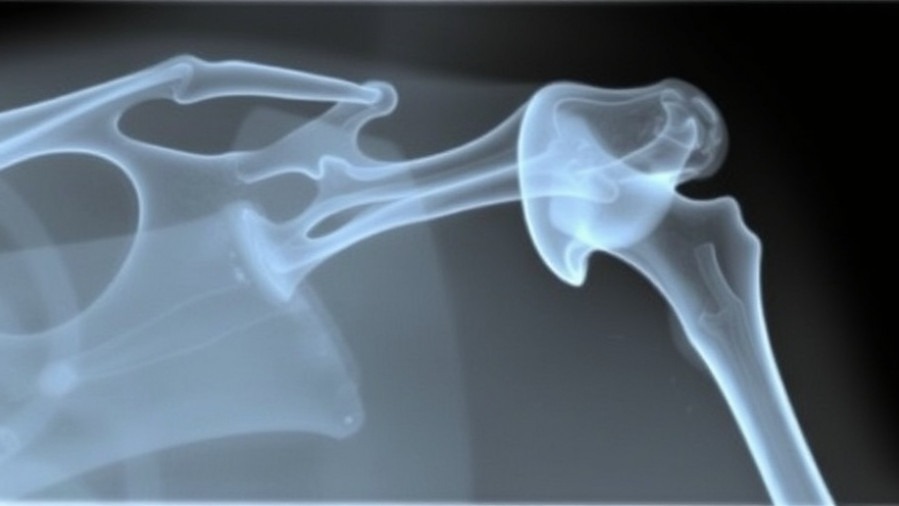

The Importance of Glenoid Bone Loss Assessment in Surgery Decisions

Evaluating Surgical Options for Glenoid Bone Loss

Understanding the intricacies of shoulder surgery is essential for both medical professionals and patients navigating their healthcare choices. According to Dr. Julie Y. Bishop, a leading orthopedist at The Ohio State University, making the right decision regarding open versus arthroscopic surgery hinges significantly on the assessment of glenoid bone loss. This exploration is particularly pertinent for the growing number of concierge medical practice owners who aim to provide personalized and comprehensive care.

Why Bone Loss Categories Matter

Dr. Bishop categorizes bone loss into three main groups: under 10%, between 10%-15%, and over 15%. In cases of less than 10% bone loss, she notes that the majority of patients would be candidates for arthroscopic procedures. However, each case is distinct, especially when considering factors like the patient’s activity level and age. For example, a young female athlete may still require an open procedure despite minimal bone loss due to the risk of recurrence of instability.

Insight into Decision-Making

For practitioners, these insights stress the importance of assessing each patient’s individual circumstances. In the “gray area” of 10% to 15% bone loss, decisions become highly individualized. For contact athletes, a Latarjet procedure might be the most appropriate choice due to the increased risks associated with their activities, while older adults may benefit more from an arthroscopic approach. This variability emphasizes the customization of care—a central philosophy in concierge medicine.

New Research Findings Enhancing Decision Accuracy

Recent studies highlight how surgical decisions are informed by more than just qualitative measures of bone loss. A study published in the Journal of Shoulder and Elbow Surgery indicated that a thorough analysis of a patient’s previous dislocations and the specifics of their shoulder anatomy significantly impacts the choice between arthroscopic and open surgeries. These findings provide an additional layer of insight, presenting concierge practice owners with actionable knowledge that can refine surgical pathways and improve patient outcomes.